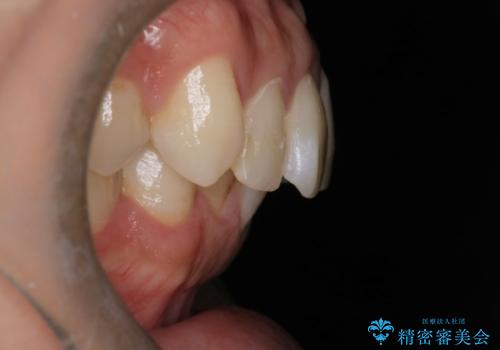

- 前歯のがたつきと口元を下げたいとのことで来院されました。

骨格的に左右差があるので正中を合わせることと抜歯矯正での口元改善は難しいことを説明させていただきました。

患者様に理解していただいた上で、インビザラインにてIPR(歯と歯の間を削る処置)を行いながら前歯のがたつきを整える治療計画を立てました。

インビザラインにて治療を行うことで、前歯のがたつきが改善されました。

左上1番目の前歯はセラミックをご希望されたので、セラミックにて被せ物の治療を行いました。

とても綺麗な前歯になりました。